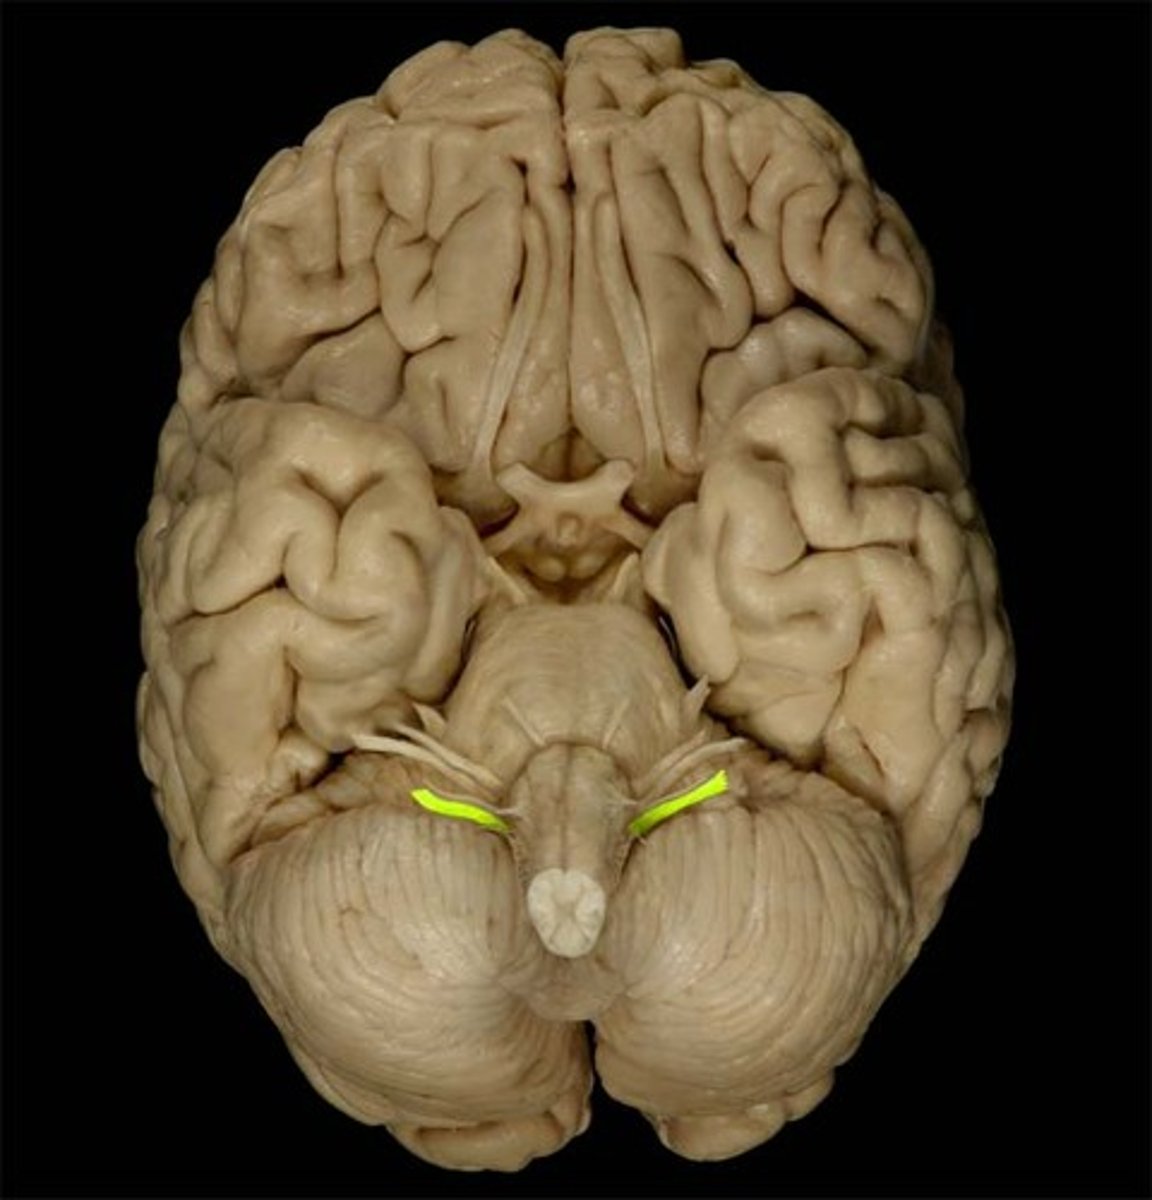

Superior Dorsal View of brain

Gyri

Sulci

Longitudinal Cerebral Fissure

Frontal Lobe

Parietal Lobe

Occipital Lobe

Central Sulcus

Lateral Sulcus

Somatomotor Area

Somatosensory Area

Cerebellum

Olfactory Bulb

Optic Chiasm

Mammillary Bodies

Pons

Medulla Oblongata